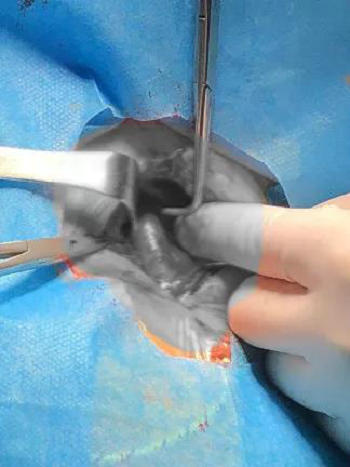

为了病人,医生们急中生智想到了另一种方法,那就是经颈总动脉入路,这种入路方式比较鲜见但更加便捷,而且医院的颈动脉手术技术成熟,创伤也不大。

主动脉弓,牛角弓,弓上血管迂曲 暴露颈总动脉

选好手术方案后就开始行动,在血管外科崔文军副主任的协助下,顺利暴露颈总动脉,预留打结线,穿刺进入颈总动脉,指引导管顺利进入颈内动脉,支架辅助行后交通动脉瘤栓塞,1小时后手术结束,排雷成功,导管退出后预留线打结,颈动脉穿刺缝合处无明显渗血,手术成功!患者很快清醒过来,顺利返回病房。经过一段时间的治疗,郭奶奶颅内的蛛网膜下腔出血也已吸收,没有致残,没有留下后遗症,整个人神清气爽,出院回家了。